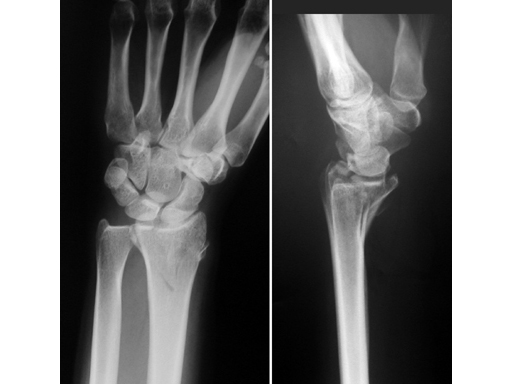

Case 1

Reversed Barton fracture 23-B3 in a 34-year-old woman after fall on outstretched hand.